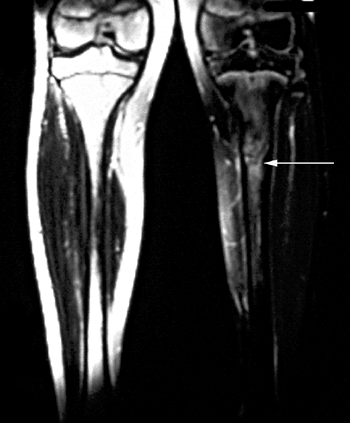

is imperative to obtain appropriate radiographs to rule out an

osteochondral fracture. If symptoms persist, magnetic resonance imaging

(MRI) may be helpful in visualizing a chondral or osteochondral defect (Fig. 32.2).

![]() |

|

Figure 32.2

Lateral image of knee [magnetic resonance imaging (MRI)] with large osteochondral defect of lateral femoral condyle after acute patellar dislocation. Arrows (solid black) point to defect in lateral femoral condyle. |